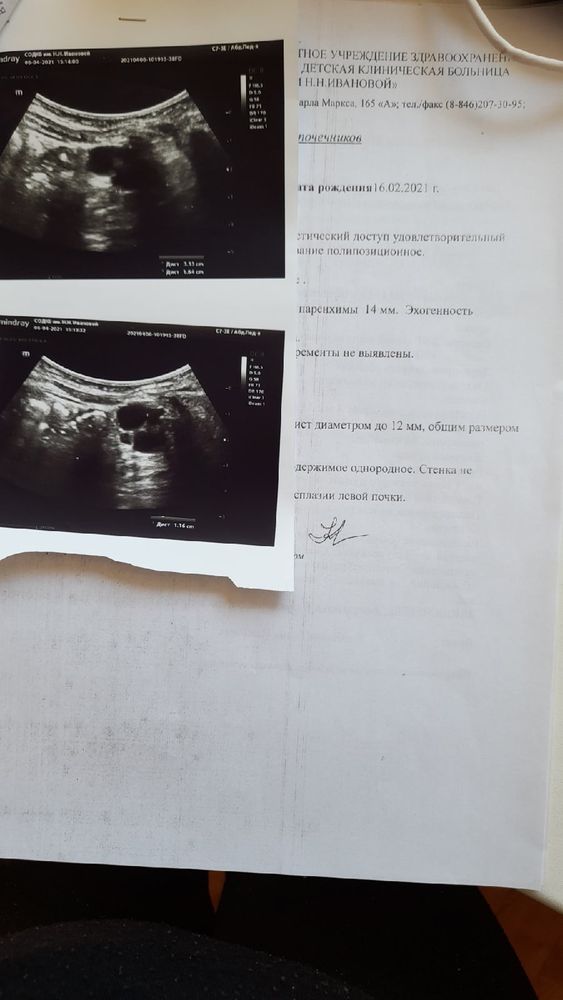

Хочу обратиться к вам за помощью! Совсем недавно я познакомилась с очень милой молодой девушкой у которой трое маленьких деток и один из них самый маленький болен неизлечимой генетической болезнью Муковисцидоз. Как это случилось думаю немногие знают, но встречала здесь на форуме подобные истории.... Вот история и результаты прикреплю ниже! При рождении ребёнка как всем известно в первые 3-4 дня жизни ребёнка берётся кровь из пяточки на 5 маркеров генетических заболеваний. Самая обычная процедура и все бы ничего если бы через несколько дней после выписки мамы и ребёнка из роддома и наслаждением материнства уже в стенах дома раздаётся звонок из генетического центра и сообщается о том что у вашего ребёнка превышен показатель крови на маркер в данной истории на муковисцидоз. А пока разговаривая с генетиком по телефону ты впервые слышишь об этом заболевании но понимаешь что есть какие то отклонения! Тебя просят пересдать кровь ребёнку! Ты вешаешь трубку и лезешь в интернет читать что же это за заболевание такое. И вот тут прочитав об этом смертельном и неизлечимом заболевании и глядя на своего спящего любимого комочка думаешь только об одном- почему именно тебя это коснулось и твоего ребёнка, за что, почему, и только бы все это оказалось неправдой! Затем процедура подтверждения следующая! Нужно пересдать кровь в определенные дни жизни ребёнка и если показатели крови опять же превышают дальше нужно ещё одно подтверждение или отрицание это сдавать анализ на потовые пробы.

Вот так и произошло наше знакомство с девушкой которой сейчас очень хочется помочь, а точнее помочь ее сыночку! Ему уже почти 5 месяцев, а должного лечения он пока не получает из-за нехватки денежных средств. И самым основным помощником в лечении, вернее в поддержании здоровья при муковисцидозе, является ингалятор, но необычный, которым дышат обычные детки при лечении бронхита, а мощный ингалятор при муковисцидозе! В Самаре в медицинских магазинах такого ингалятора нет нигде, нашли только на одной из торговых площадках. Стоимость не такая высокая, но осилить семья не может!